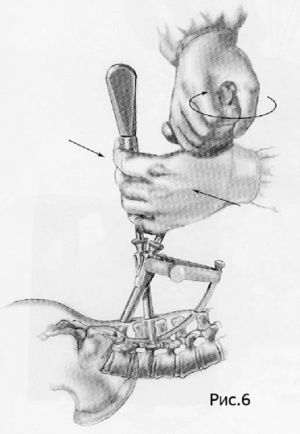

Хирургическое лечение спондилолистеза заключается в фиксации «разболтанных» позвонков титановыми винтами. Винты вводятся в позвонки через дужки позвонков (с лат. «педикули»), поэтому такая фиксация называется «транспедикулярной». Данный метод фиксации позвонков был впервые применен Roy-Camille в 1963г. и используется благодаря своей высокой эффективности по всему миру до настоящих дней.

Наиболее современным методом фиксации в настоящий момент является миниинвазивная технология введения винтов через небольшие разрезы. Этот метод позволяет меньше травмировать мышцы разгибатели позвоночника при введении винтов, а также более быстрому выздоровлению пациента и возвращению к обычному образу жизни, активному отдыху и работе. Технология данной фиксации заключается в использовании канюлированных винтов, т.е. винтов с отверстием в центре. В начале в тело позвонка вводится спица, а уже по спице вводится винт. Удаление грыжи диска и введение кейджа в межтеловой промежуток производится через тот же разрез, что и введение винтов.